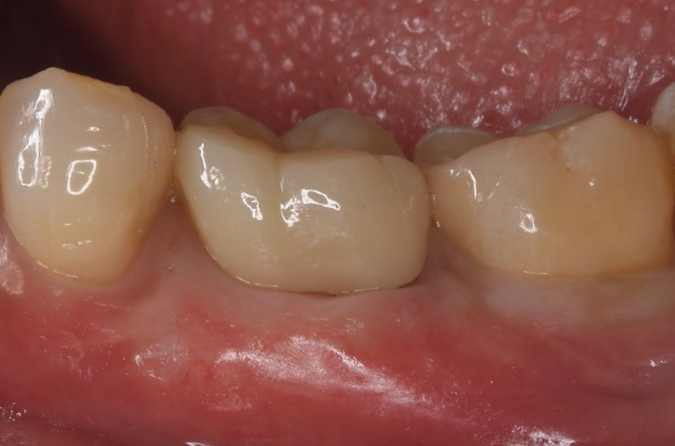

症例2

| 項目 | 詳細 |

|---|---|

| 患者様データ | 67歳 女性 |

| 来院時の主訴 | 「歯周病を治して一生自分の歯で食事を摂りたい。」 |

| 医院の診断 | 重度歯周病とう蝕 |

| 通院期間 |

1年6ヶ月 |

| 来院回数 | 10回 |

| 治療費 | 総額:480,000円(税抜) 歯周基本治療は保険適用診療 【内訳】 《保険適用診療》 歯周病検査・歯磨きや生活習慣指導・歯石取りクリーニング 《自費診療》 歯周組織再生療法240,000円(費用は範囲によって異なります。)、セラミック治療120,000円×2 |

| リスクと副作用 | メインテナンスが必要、正しい歯磨き習慣が必要不可欠 |

| ここがこだわりのポイント!☝ | 重度の歯周病の治療には長い治療期間がかかります。重症になるまでに時間がかかっている分、治るのにも時間がかかるからです。この症例の場合、患者様に頑張っていただいた結果、歯周ポケットが8mm→2mmに改善し、健康な歯周組織(骨・歯肉)を獲得することができました。 一生涯自分の歯で食事ができるよう、引き続きサポートを続けさせて頂きます!本当によく頑張って下さいました。お疲れ様でした! |